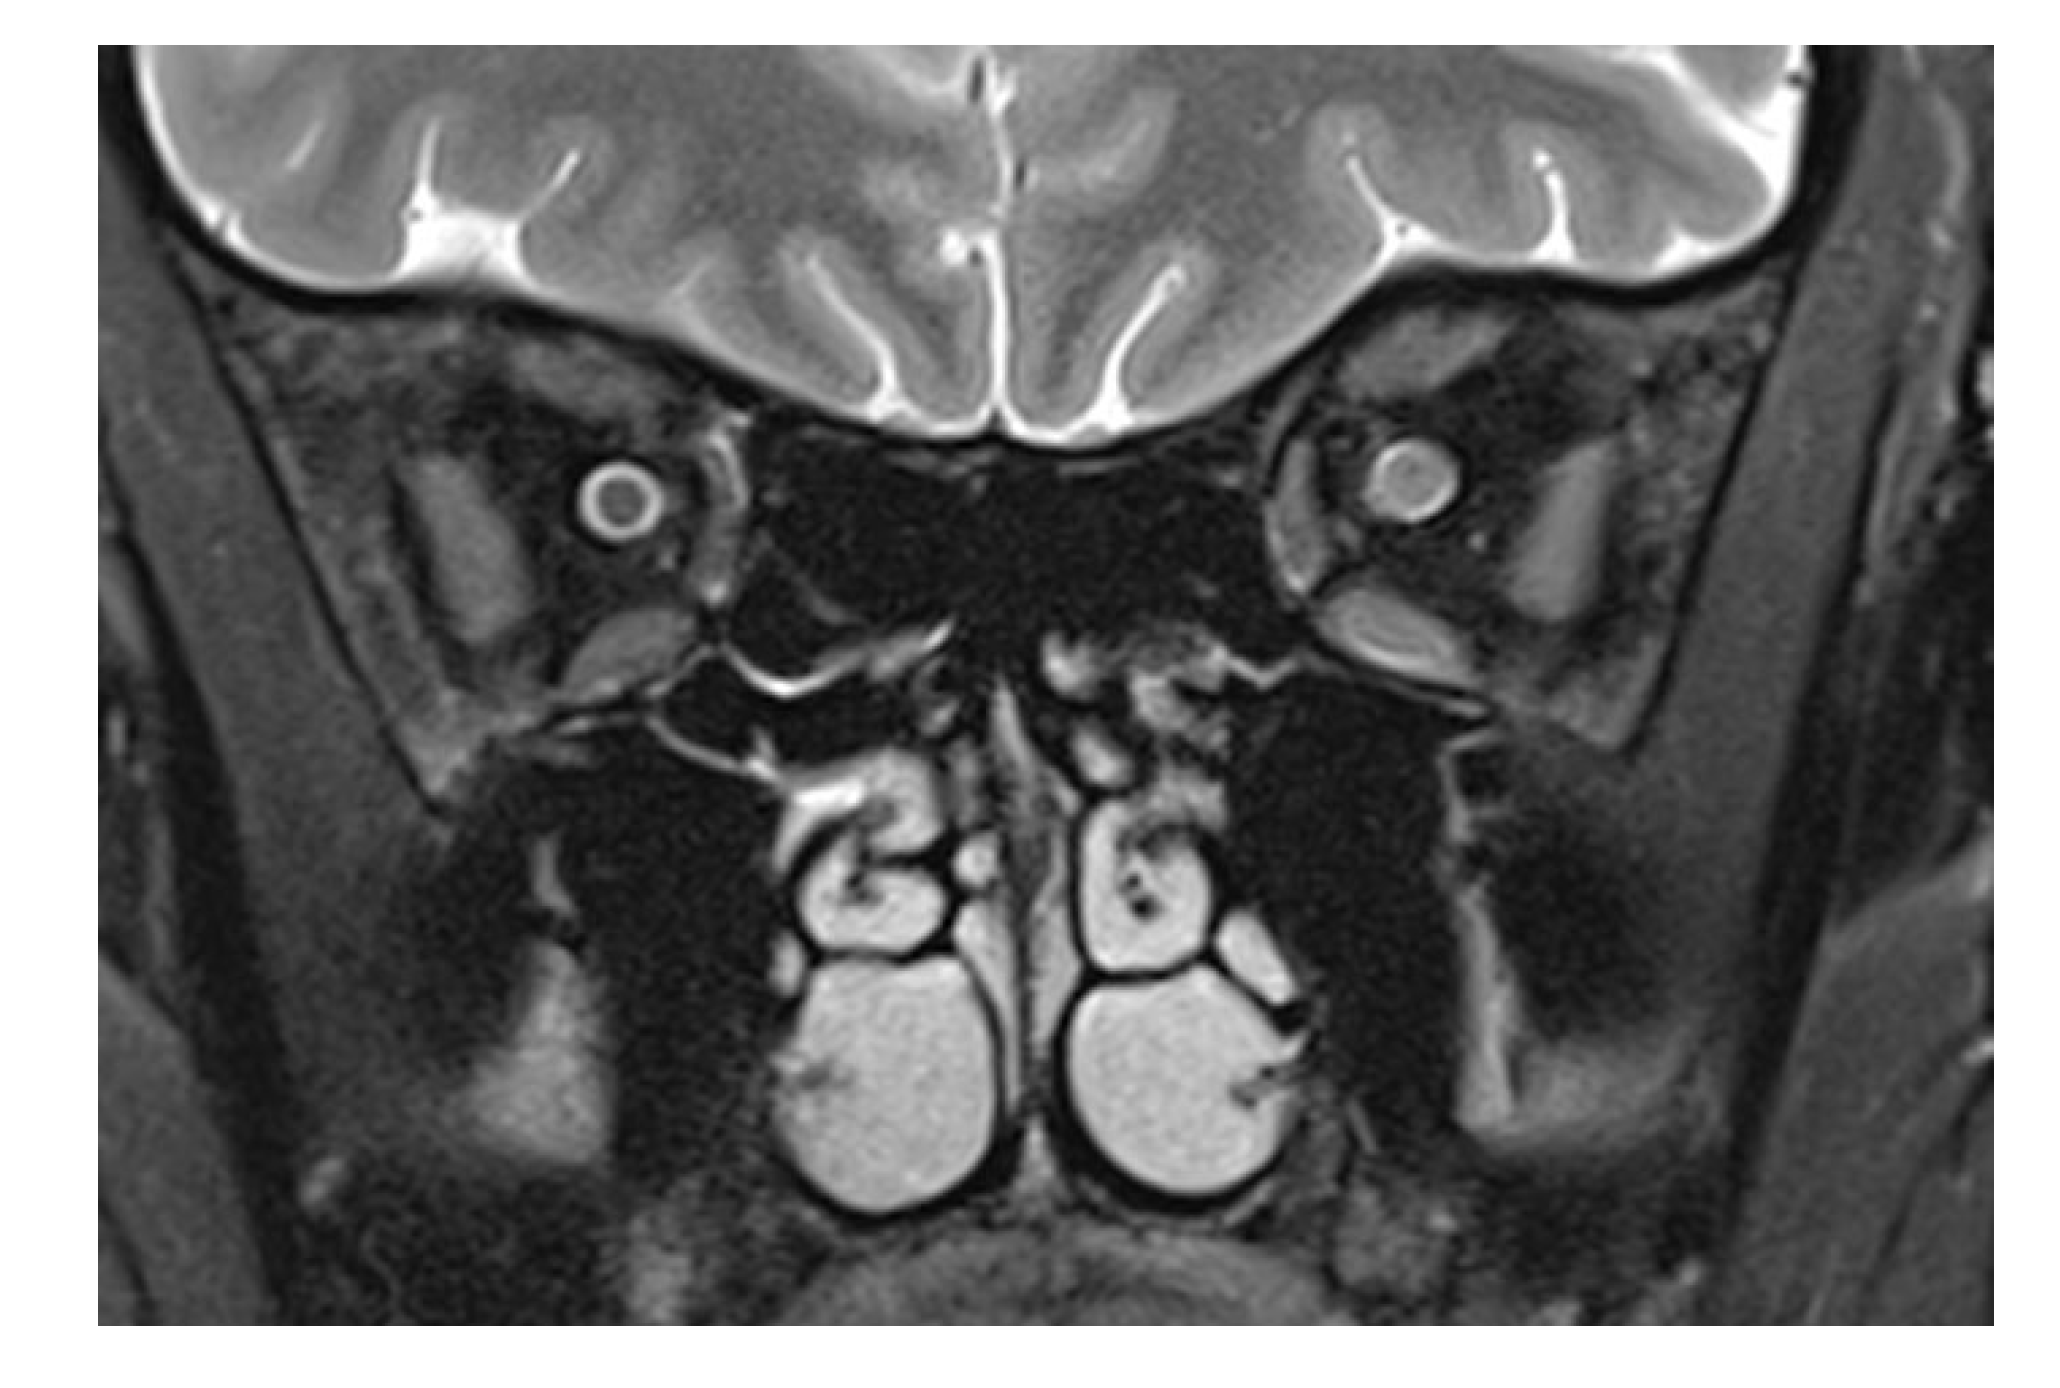

The patient presented here had direct trauma to the right eye, and MRI was performed after full ophthalmological examination, only hours after the trauma in a conscious and cooperative patient. The trauma was a “perforating stab wound” [4] but missing the globe. The only sequela clinically visible was a conjunctival tear. CT excluded soft tissue changes, fracture, and foreign bodies in the globe and orbit. On MRI, changes in the optic nerve (and impossible to be seen on CT) were noted. This structure showed an opacification of the subarachnoid space, compatible with hemorrhage: an increase in the T2 signal of the optic nerve anterior to the inner opening of the optic canal; an increase in signal intensity on the diffusion-weighted b1000 image; and a decreased signal in the ADC map in the same location. The obliteration of the subarachnoid space around the optic nerve was different from what is commonly seen in the enlargement of an optic nerve. (For comparison, Figure 2 shows a T2-weighted image of an inflamed optic nerve in a patient with multiple sclerosis. There, the nerve supplants the subarachnoid space, which in comparison to the right and unaffected side is less wide).

Figure 2.

T2-weighted frontal image in a multiple sclerosis patient with optic neuritis. While the subarachnoid space has a normal diameter on the left, an enlarged optic nerve encroaches in the same space, recognizable by the smaller liquor-filled rim of the nerve. Leakage of cerebrospinal liquor after direct laceration of the sheath, however, cannot be counted out. The diffuse signal increase of the nasal retrobulbar space in Figure 1f,g may be explained by cerebrospinal liquor leaking from an injured optic nerve sheath and by edema.